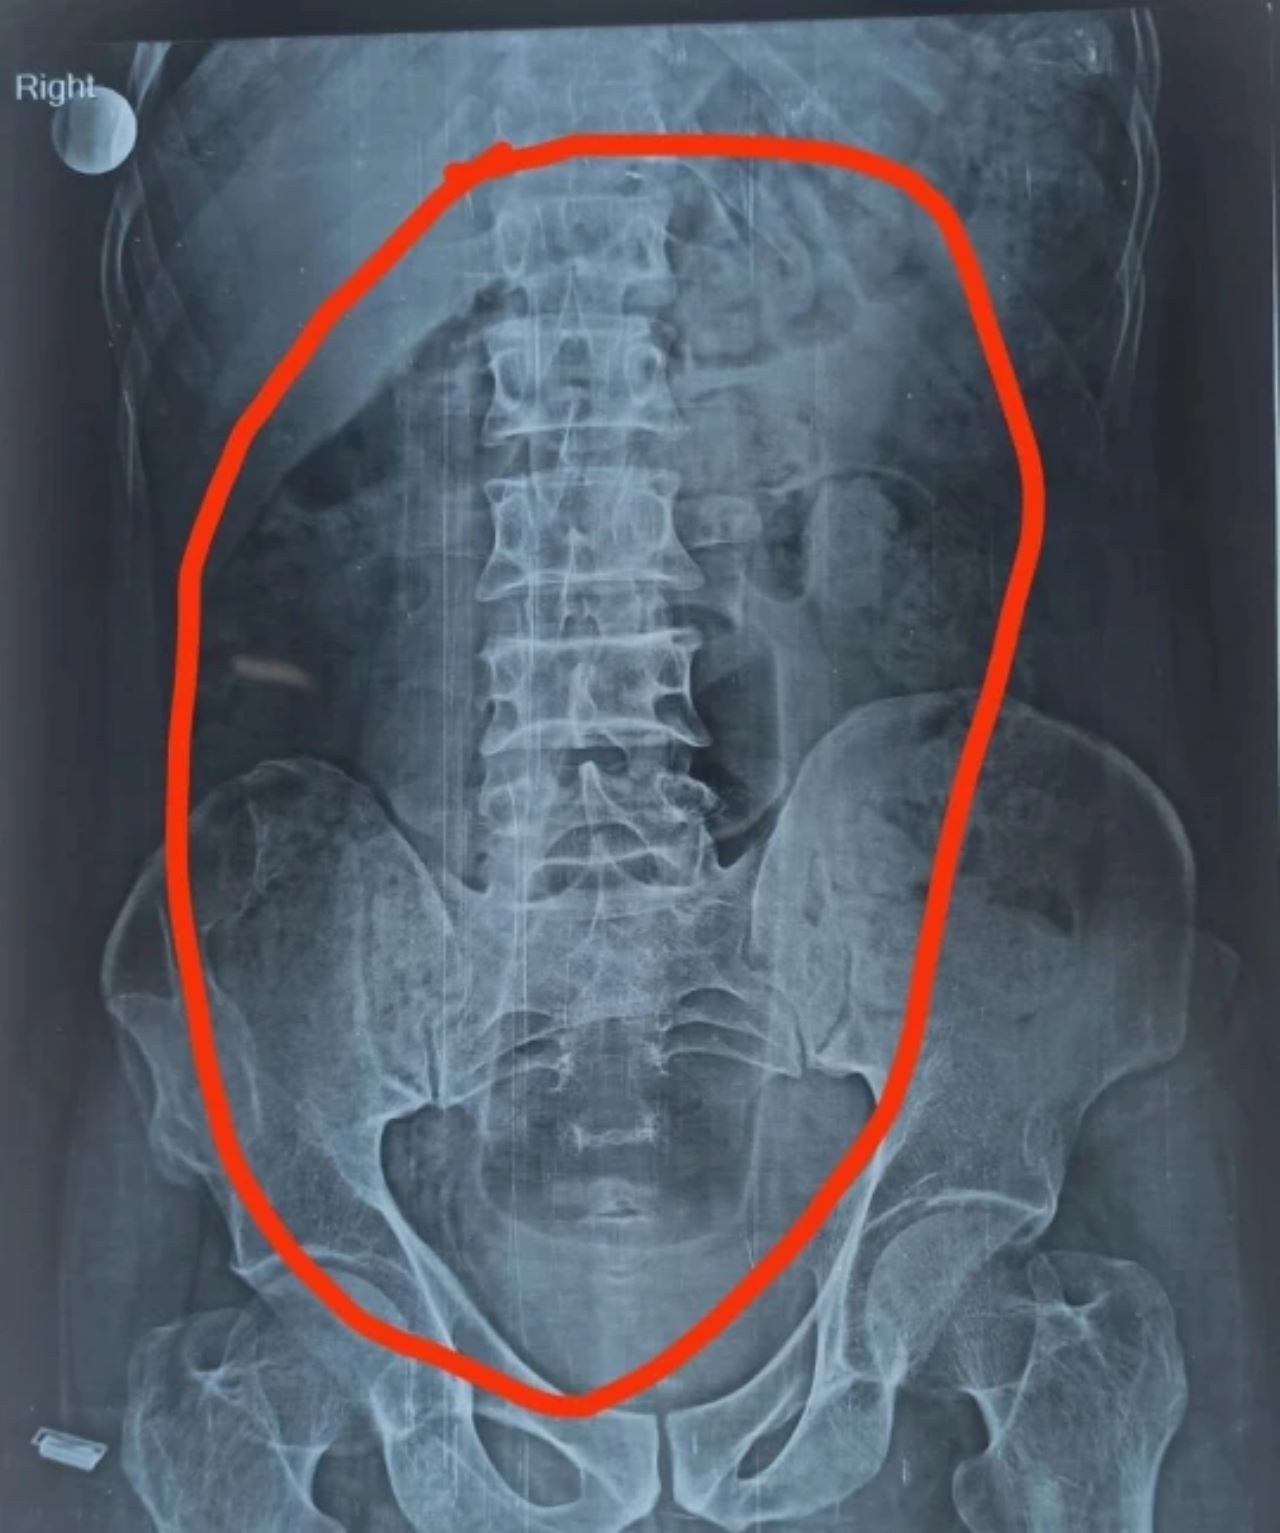

Sebelum pembedahan dilakukan, pemeriksaan sinar-X telah mengesan kehadiran botol tersebut di dalam perutnya sebelum doktor mengambil tindakan lanjut.

Selepas pembedahan dibuat, objek yang tersekat pada perut lelaki itu adalah botol minyak rambut Nihar Shanti Amla berwarna hijau.